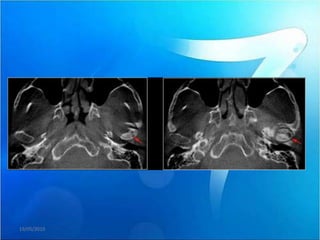

Se le realiza el estudio de tomografía volumétrica, las imágenes

axiales y coronales muestran zonas erosivas en ambos cóndilos

mandibulares, e imágenes hipodensas compatibles con probable

quiste subarticular.

Se le realizael estudio de tomografía volumétrica, las imágenes axiales y coronales muestran zonas erosivas en ambos cóndilos mandibulares, e imágenes hipodensas compatibles con probable quiste subarticular. 19/05/2010

• 82.